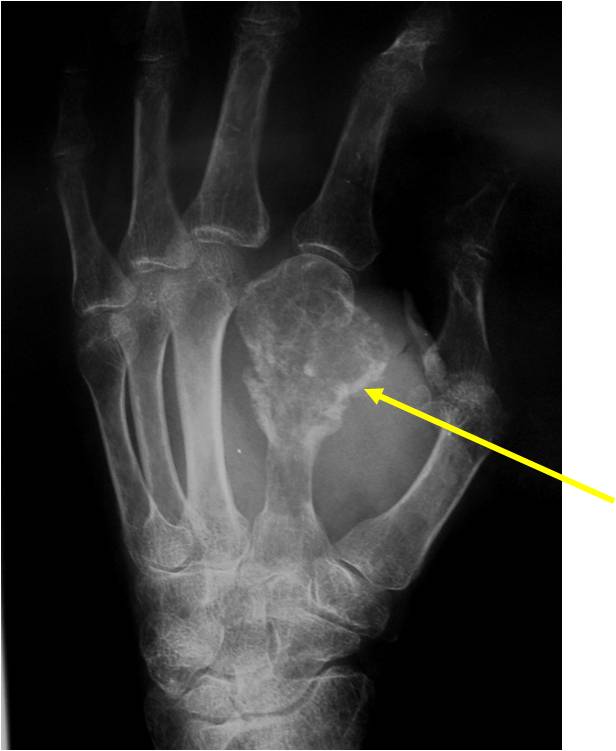

Geographic Lesion Bony Expansion Minimal Calcification Some Enchondromas do not calcify

Geographic lesion Stippled calcifications in lesion Phalanx is expanded Significant endosteal scalloping No cortical destruction No soft tissue extension Cortex Scalloped and Expanded